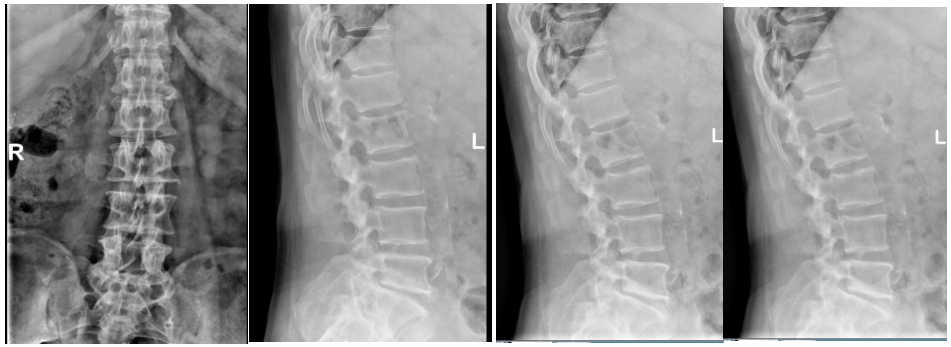

原来啊,在 20 年前他因腰椎问题接受了腰 5 骶 1 开放手术,但随后他的腰 4/5 节段出现不稳,腰部疼痛逐渐加剧,并伴有左下肢麻木、发凉,到了最近,他连日常行走站立都变得异常困难。

在近乎绝望之际,马叔叔得知河南省直第三人民医院能开展腰椎微创手术,抱着最后一丝希望前来就诊。河南省直第三人民医院脊柱微创外科贺毅团队对他的病情进行了详细评估:

贺毅团队一致认为,传统开放手术风险过高,不适合马叔叔的情况。经过反复讨论,最终为他制定了内镜下腰 4/5 椎管减压+腰椎间盘切除+椎间植骨融合内固定术的微创手术方案。